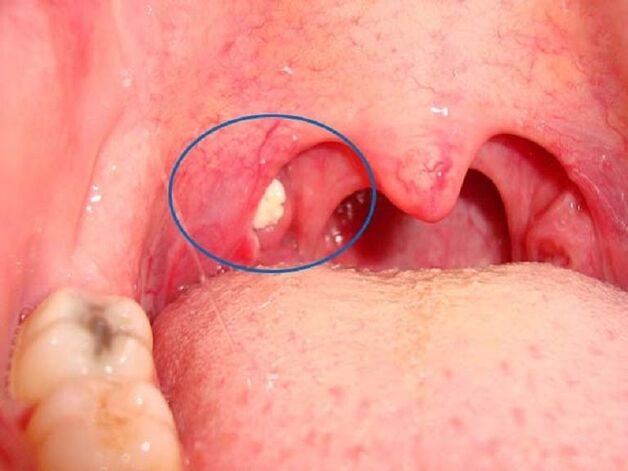

Sỏi amidan là những khối màu trắng hoặc vàng xuất hiện trên bề mặt amidan. Được đánh giá là không gây nguy hiểm cho cơ thể nhưng sẽ tạo cảm giác khó chịu trong quá trình ăn uống, nói chuyện. Và các sỏi amidan này thường dễ quan sát bằng mắt thường qua gương nhỏ.

– Nhìn thấy các chấm trắng nhỏ ở amidan khi quan sát qua gương

Sỏi amidan là những đốm trắng, vàng và dễ nhìn thấy khi quan sát qua gương